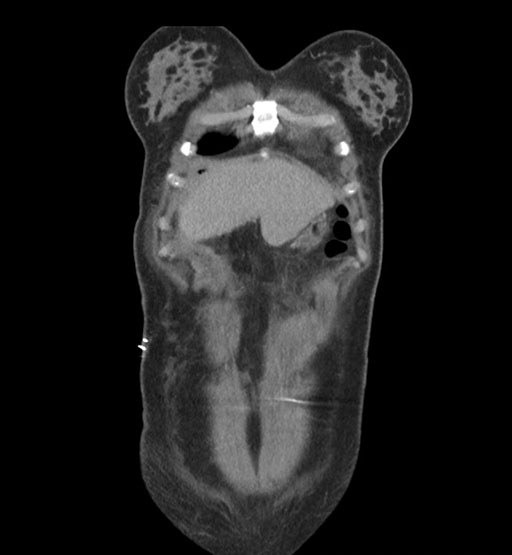

Coronal Arterial

Coronal Venous